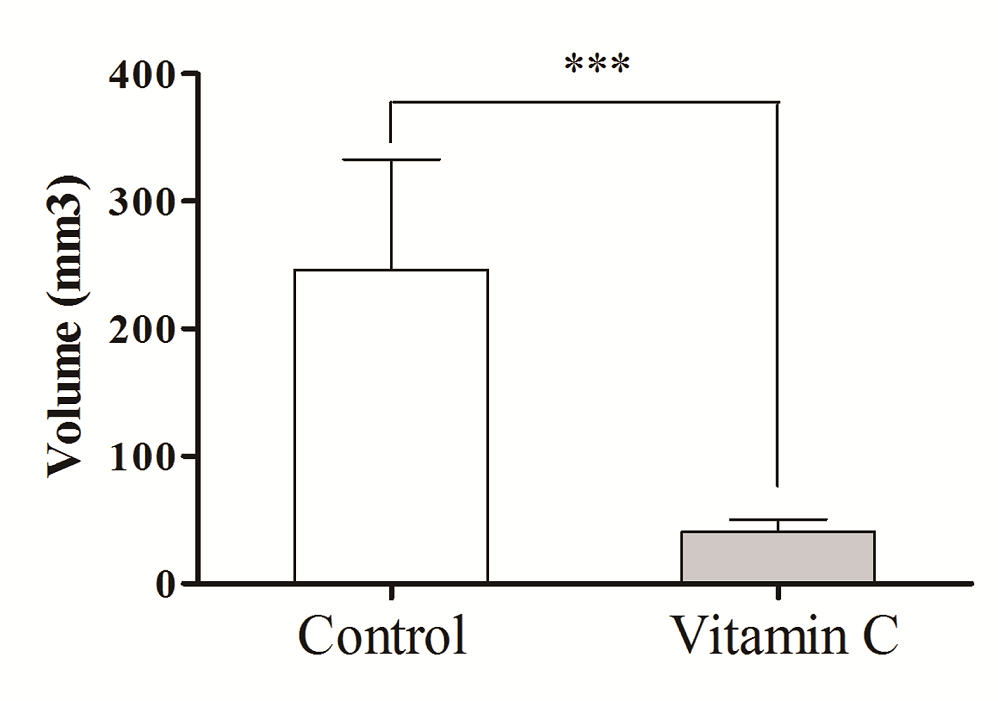

At the end of the 2 week treatment period, rats in the two experimental groups had a second laparotomy performed after a lethal dose of 50% chloral hydrate. Intra-abdominal endometriotic lesions obtained from the vitamin C group and the control group were evaluated (Table 2, Figure 3 and Figure 4). The lesion size of the abdominal wall of each rat was measured by a uniform scale of length × width × height (cm), thus resulting in 14 sets of data obtained from each group of rats. After removal of the lesion, selected portions of these tissues were randomly taken and stored in 10% formaldehyde solution for histopathological examination. The remaining tissues were preserved in liquid nitrogen.

Figure 3.

Figure 3.— Size comparison of endometriotic lesions between vitamin C and control groups. (A and B) Representative endometriotic lesion of vitamin C group. (C) Representative endometriotic lesion of control group.

Figure 4.

Figure 4.— Comparison the size of endometriotic lesions between control group and vitamin C group.

We measured no significant difference in body weight between rats in the vitamin C group and the control group (Table 1). However, intra-abdominal lesions in the abdominal wall of rats were reduced after intraperitoneal infusion of vitamin C solution compared with controls. In the vitamin C group, no abnormal endometriotic lesions were found in the abdominal wall of one of the rats following the second operation. There were also no observable endometriotic lesions on one side of the abdominal wall in another vitamin C-treated rat. Tabulated lesion volume of the vitamin C and control groups of is shown in Table 2, as well as Figures 3 and 4.

Foods that are rich in vitamin C can reduce the risk of endometriosis [19]. Vitamin C is a water-soluble vitamin, which functions as an antioxidant by directly scavenging oxygen free radicals. Because vitamin C can scavenge oxygen free radicals it can accelerate repair of damaged endometrium [20], and effectively inhibit endometriosis [21]. In endometriosis, reducing the lesion while limiting the degree of fibrosis around the lesion is clinically important. In our study, we administered vitamin C solution and physiological saline intraperitoneally, and compared the size of endometriotic lesions after perfusion. Lesions in the vitamin C group were significantly reduced compared with those in the control group (Table 2, Figures 3-4), and even the original endometriotic lesions in three of the rats given vitamin C disappeared. Our findings suggest that vitamin C has a therapeutic effect on endometriosis, and could also be useful in treatment of peripheral fibrosis.